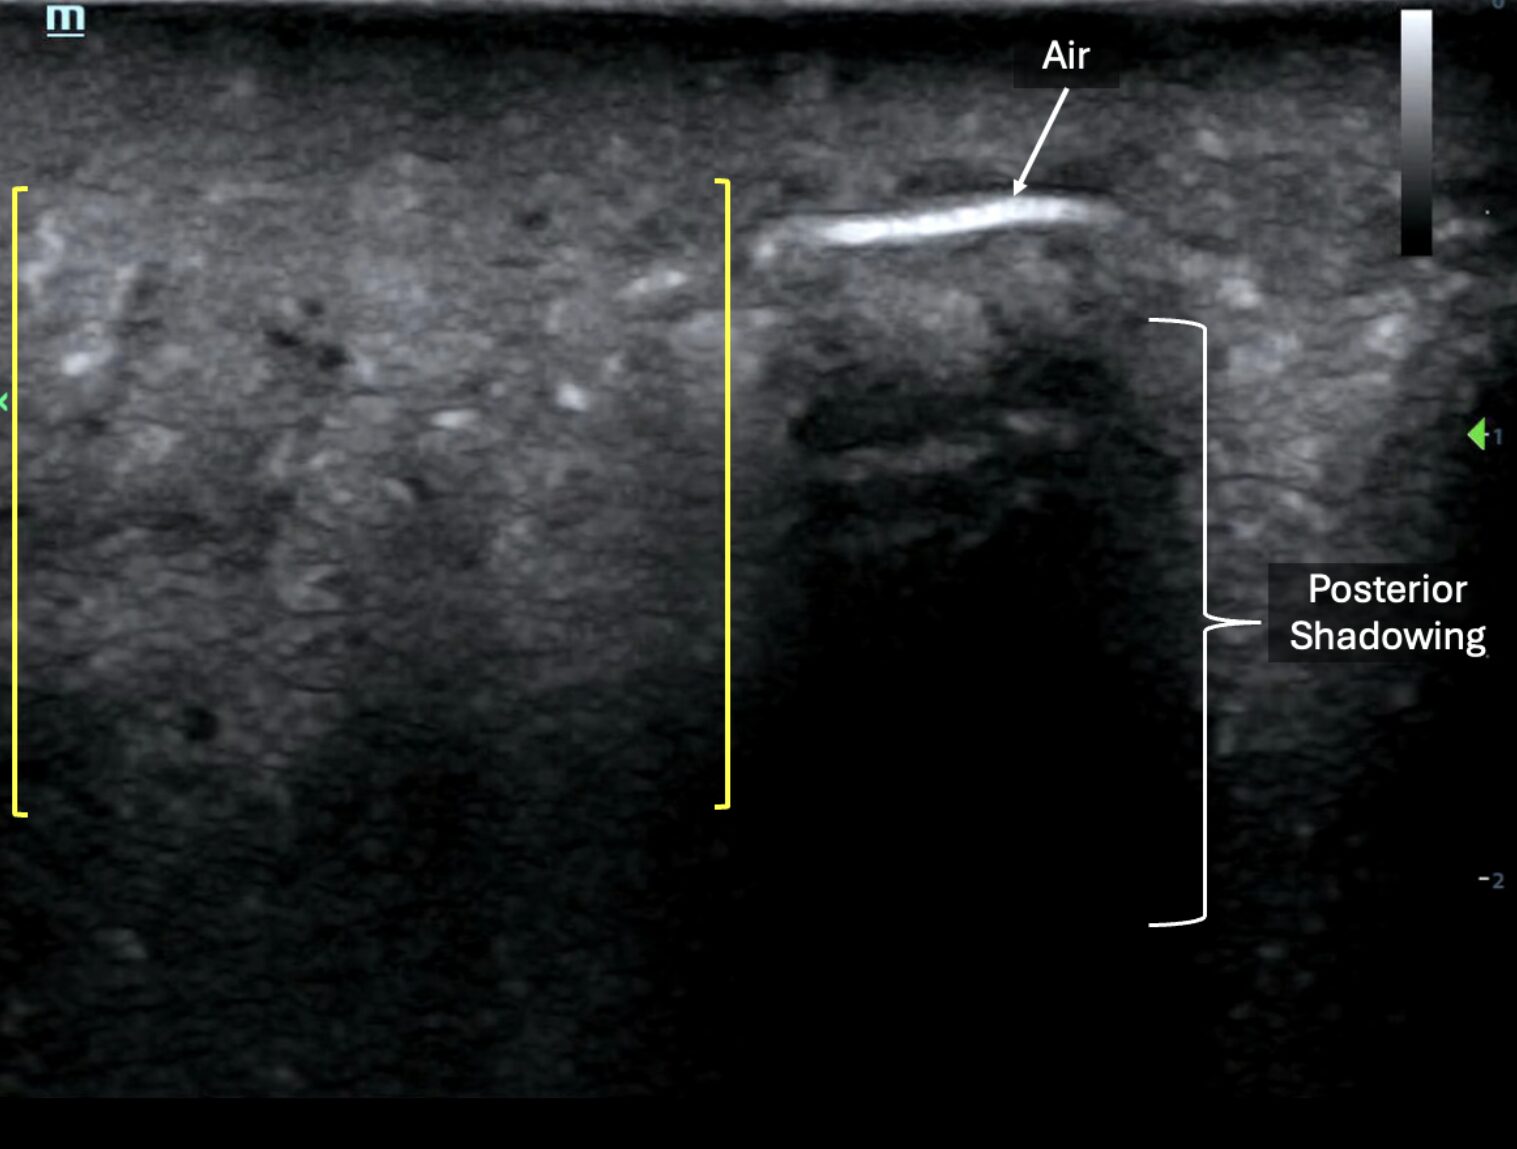

In the case below, note the subcutaneous emphysema appearing as a single linear hyperechoic line with posterior shadowing. Adjacent to that line appears dynamic sparkling echogenic material suggestive of mobile fluid (possibly purulence), interspersed with gas bubbles (within yellow brackets) (Image 4, Video 3).

Image 4: Still image demonstrating subcutaneous air and posterior shadowing (hyperechoic line to the right of the image) and purulence (left side of image). Images courtesy of Dr. Shepherd and Dr. Alerhand.

Video 3: Video clip of the above still image demonstrating posterior shadowing and purulence. Images courtesy of Dr. Shepherd and Dr. Alerhand.

Below is another example of anechoic layering of fascial fluid (left side of image) tracking deep to subcutaneous tissues juxtaposed next to hyperechoic foci of air with posterior shadowing, indicating subcutaneous emphysema (right side of image) (Image 5, Video 4).

Image 5: Image demonstrating presence of subcutaneous emphysema (right side of image) and layering of fascial fluid (left side of image). Images courtesy of Dr. Shepherd and Dr. Alerhand

Video 4 : Video clip of the above still image demonstrating subcutaneous emphysema and layering of fascial fluid. Images courtesy of Dr. Shepherd and Dr. Alerhand